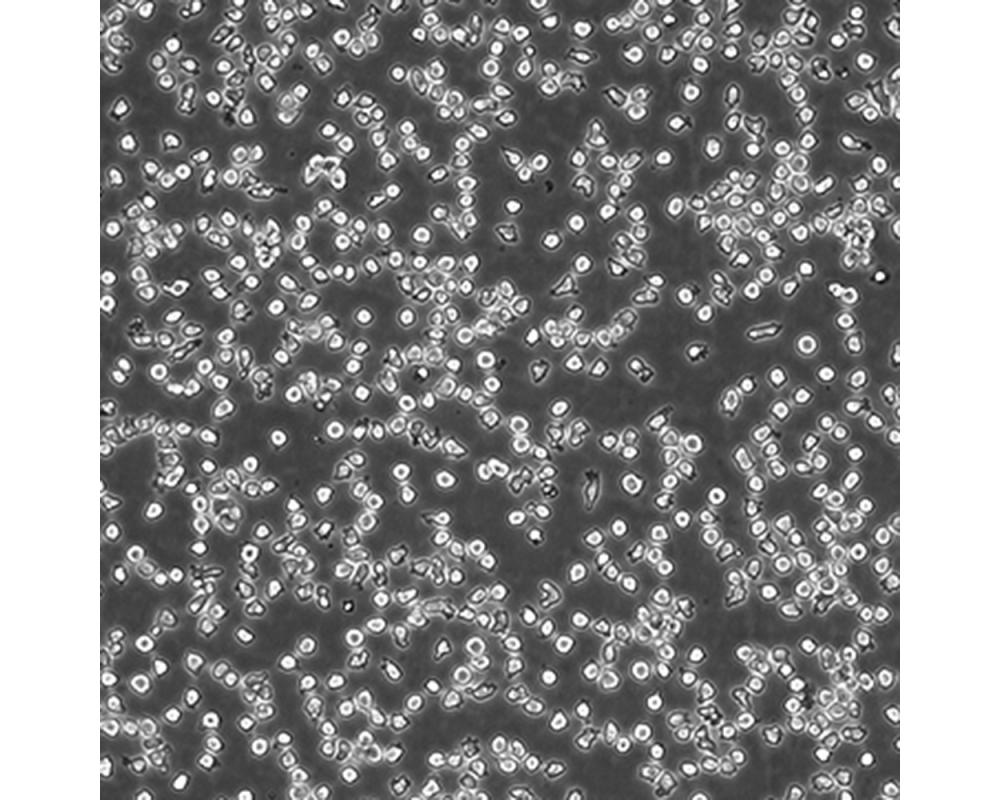

產品名稱 SUP-T1

中文名稱 人T淋巴細胞瘤細胞

組織來源 T淋巴瘤細胞;男性

生長特性 懸浮

培養(yǎng)基 1640,90%;FBS,10%;雙抗。

傳代方法 Maintain cultures at a cell concentraion between between 1 X 10(5) and 1 X 10(6) viable cells/ml.

培養(yǎng)條件 Atmosphere: Air, 95%; CO2, 5%。Temperature: 37℃